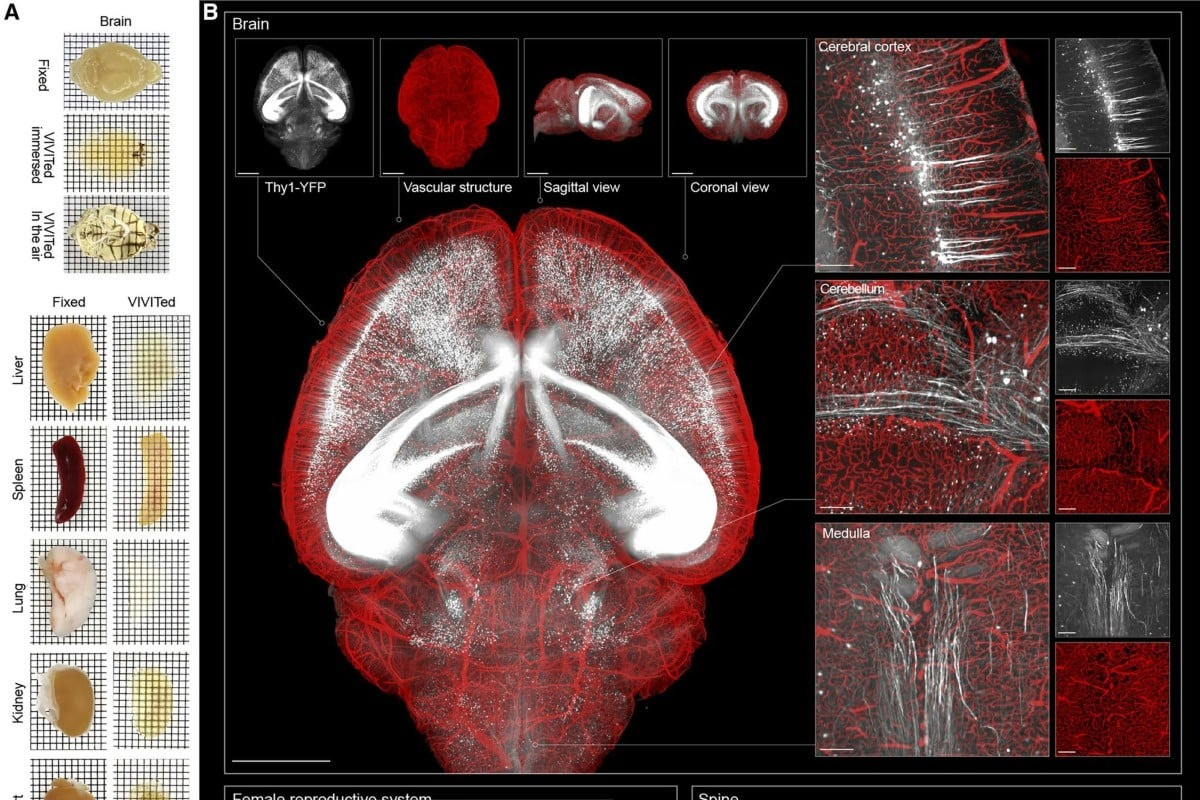

5. Kỹ thuật mới của Trung Quốc làm cho hình ảnh não trở nên trong suốt

Một nhóm nghiên cứu thuộc Đại học Thanh Hoa ở Trung Quốc vừa phát triển một phương pháp mới để làm cho các cơ quan như não hoặc tim trở nên trong suốt, đồng thời vẫn giữ nguyên cấu trúc sinh học bên trong. Kỹ thuật này mang đến hình ảnh ba chiều rất sắc nét và sống động, giúp quan sát chi tiết tế bào và phân tử mà không cần phải làm tổn thương mô.

Phương pháp mới hứa hẹn mở ra bước tiến lớn trong nghiên cứu giải phẫu học và y học hình ảnh, cho phép các nhà khoa học khảo sát phần sâu bên trong cơ quan ở cấp độ tế bào một cách trực quan và chính xác hơn. Điều này có thể hỗ trợ khám phá quy mô lớn về cấu trúc và hoạt động sinh học, từ đó thúc đẩy các ứng dụng trong chẩn đoán và nghiên cứu bệnh.